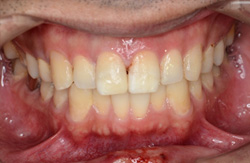

![]() |

治療後の写真 |